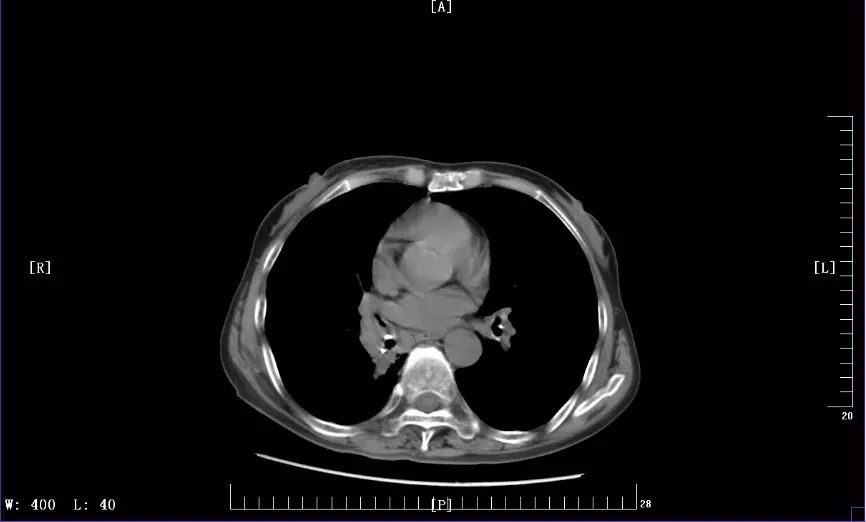

下圖是徐麗參加KEYNOTE-407臨床試驗(yàn)前后CT影像對(duì)比圖:

2018年12月最近一次治療后CT影像